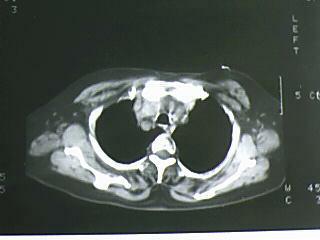

以下是引用bmw011在2009-4-14 19:14:00的发言:[br]右肺继发型肺结核---纵隔淋巴结多发钙化----左肺支扩。支持

以下是引用杀毒软件在2009-4-14 17:52:00的发言:[br]考虑---右肺继发型肺结核---纵隔淋巴结多发钙化----左肺支扩

以下是引用黑白光影在2009-4-14 20:36:00的发言:[br]右肺继发型肺结核;左下慢性支气管炎性病变。